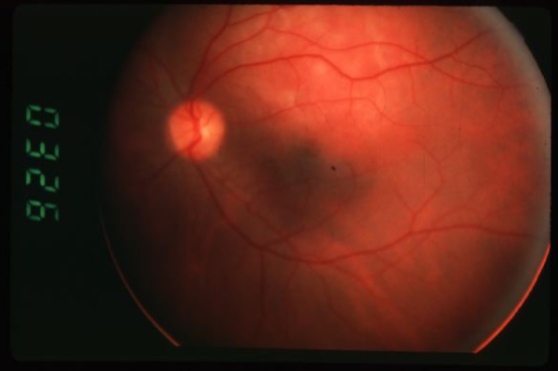

choroidal melanoma

melanoma

melanoma

melanoma

melanoma

melanoma

melanoma

melanoma

melanoma

melanoma

melanoma

melanoma

melanoma

melanoma

melanoma

melanoma

melanoma